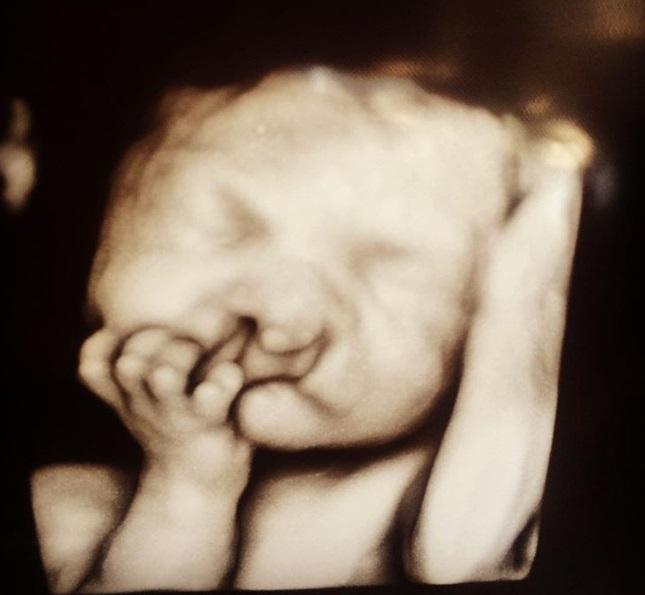

Se spune că nimic nu se poate compara cu bucuria de a deveni părinte! Doi tineri au mers la medic ca să facă ecografie și să își vadă bebelușul, doar că în scurt timp au trăit un adevărat șoc și au simțit că întreaga lume li se prăbușește! Deși au fost sfătuiți să facă avort, cei doi părinți au refuzat. Ce s-a văzut în ecografia 3D?

Timpul a trecut și cei doi s-au dus la medic, ca să facă o ecografie. Totuși, bucuria lor a dispărut rapid atunci când au privit monitorul aparatului și au realizat că ceva nu este în regulă.

Medicul le-a spus atunci că bebelușul are chiul deformat și i-a sfătuit să se gândească la un avort. Totuși, Sara și Chris și-au făcut curaj și au als să își iubească băiatul indiferent de modul în care arată.

Cel mic s-a născut și într-adevăr, chipul său arăta cumplit de deformat, precum s-a văzut la ecografie. Totuși, cei doi părinți nu și-au pierdut speranța și au conitnuat să lupte, asigurându-i băiatului operațiile necesare.